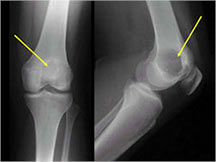

- Sites: 50% of cases located in knee area

- Distal femur, proximal humerus, proximal tibia

- Permeative lesion with indistinct border that is poorly marginated

- Osteolytic and expansile on X-ray with very little osteoid production

- Cortical destruction and soft tissue extension are common

- Pathologic fracture (25%-30%)

- Expands contour of bone and may appear similar to an ABC (aneurysmal bone cyst)